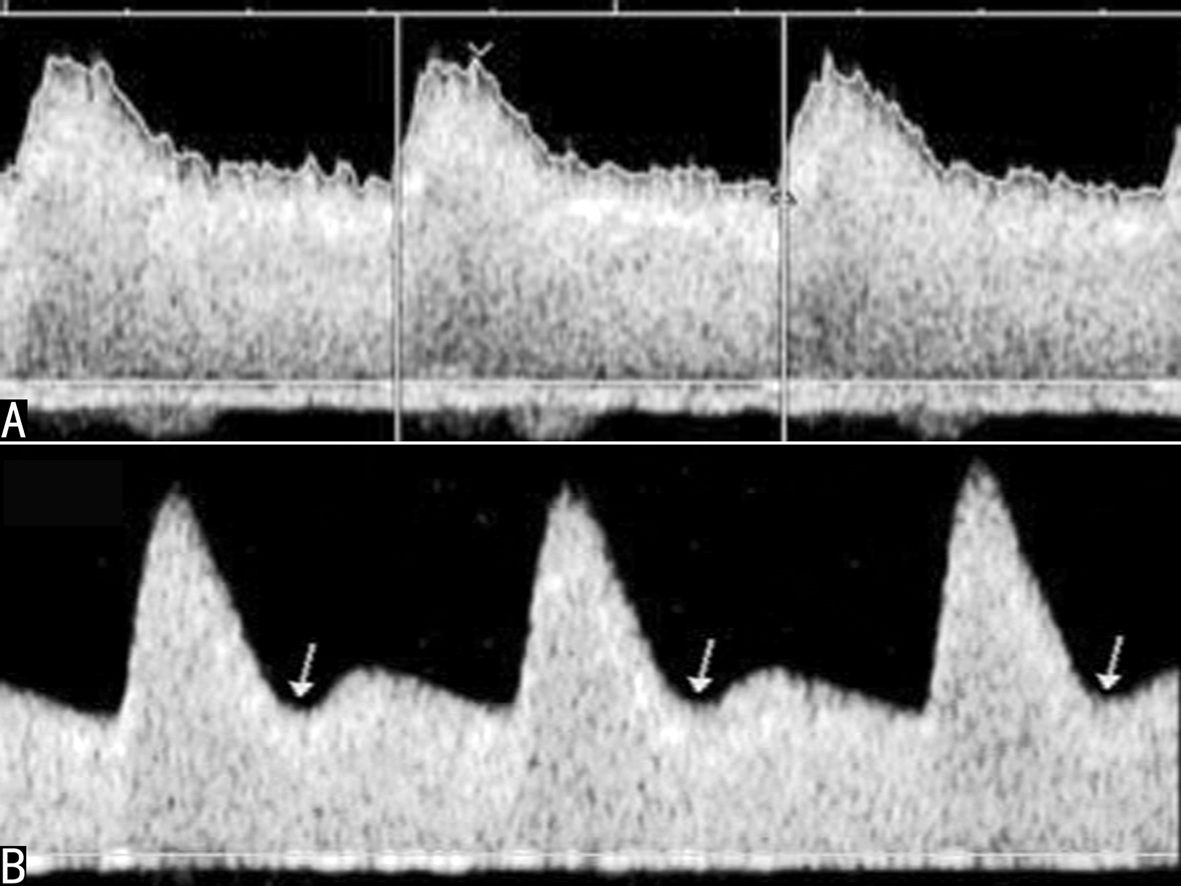

(三)子宫动脉血流速度曲线及正常参考值

尽管在月经不同时期子宫动脉血流有所不同,非孕期子宫动脉基本为高阻力血流频谱(图3A),国内一组研究资料统计了50例20~35岁健康非孕期妇女的子宫动脉血流,主要参考值:RI 0.79 ± 0.05,PI 2.08 ± 0.47,S/D 5.09 ± 1.26。从妊娠第6周开始子宫动脉血流即开始增加,并且主要表现为舒张期血流的增加,阻力下降,到第10周时下降就已经很明显(表1、图3B),随着妊娠的继续,子宫动脉的血流峰值速度逐渐增加,阻力指数和搏动指数逐渐降低(表1、图4C),至足月妊娠时形成典型的低阻力型血流(图4D)。

图3非孕期和妊娠期子宫动脉血流变化

A:非孕期子宫动脉显示高阻力血流速度曲线 B:11周妊娠子宫动脉显示舒张期血流速度增加

图4孕期子宫动脉血流变化

C:30周妊娠子宫动脉显示舒张期血流速度明显增加;箭头示子宫静脉持续、匀速的血流速度曲线;D:38周妊娠子宫动脉显示典型的低阻力型血流速度曲线

子宫静脉显示为低速、均匀的血流(图4C),随着妊娠周数的增加,也可发现其平均血流速度的增加。出现搏动性血流可能与不良妊娠有关。